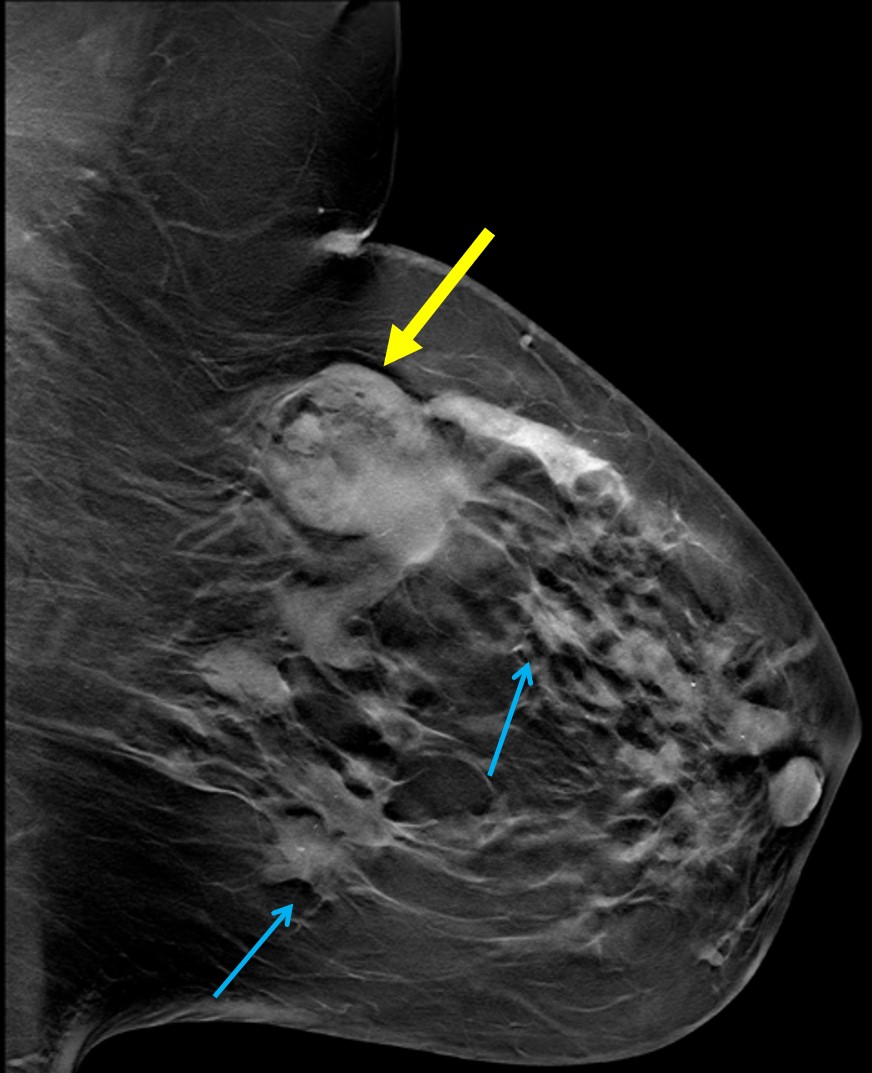

The most common cause of skin metastases in adult women is primary breast carcinoma, which comprises about 70% of cases [1]. Skin metastases have non-specific clinical appearances, making it challenging to differentiate them from other benign conditions [1]. We present a case of a 52-year-old female with type II diabetes and a three-month history of refractory skin lesions who did not respond to anti-inflammatory treatment. The patient subsequently complained of a right breast lump, evaluation of which led to the diagnosis of bilateral synchronous invasive lobular carcinoma.